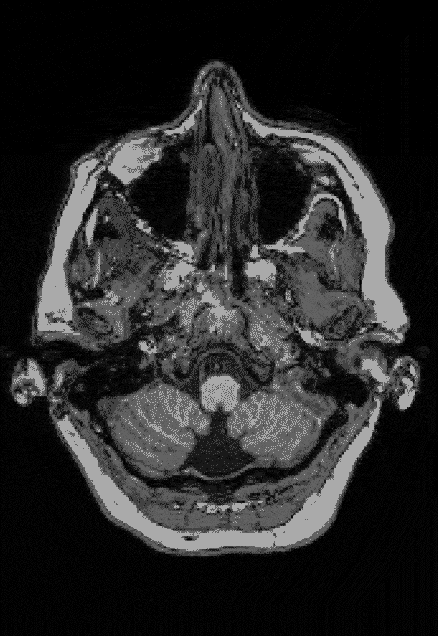

Elyse G. found out she lacked most of her left temporal lobe when she was 25 years old. The brain region is typically crucial for speech and language — but until her brain was scanned (three views shown), no one knew Elyse was missing hers.

Looking at her brain scans is a different story. It’s as if someone has knocked over a bottle of ink. The darkness pools inside her skull near her left ear, a puddle of fuliginous black. Inside the splotch, there’s no white matter or gray matter, no blood vessels or tissue at all.

Elyse says you don’t have to be a neurosurgeon to spot what’s different about her brain: “There’s a big honking piece missing!”